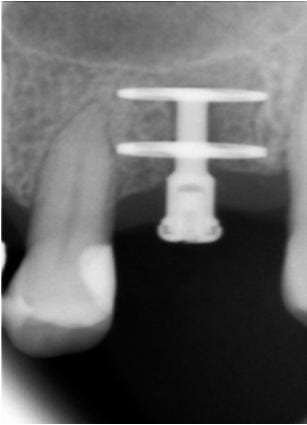

Rorschachwhite tx6rqr - Eugenol

Tiens Pluton, un 4.5 par 12, j'aurais du poser un 4 je me serais fait moins peur :-)

Mais ce n'est pas pour l'axe que je le poste, juste regarde le niveau osseux à trois mois d'écart, le pilier de cicat a été vissé le jour de la pose le 17/09 !

AMHA c'est LE + de cet implant : la stabilité osseuse.

J'ai les mêmes RX pour tout ceux que j'ai posé depuis le début de l'année.

CC.

Photo pluton1b h9n4ea - Eugenol

quoi ton axe...il est bien placé ton implant....bon pour pinailler, un chouilla plus mésial pour être parfait

j'avais un peu peur de mêler expansion et cet implant...mais non, comme sur des roulettes...

faut dire qu'on est aussi aidé par des forets particulièrement sécants...et donc on peut les faire tourner à très faible vitesse...juste pour finir d'aménager le logement implantaire...

et comme il n'est pas trop conique...moins de risques finalement de péter la corticale à l'insertion de l'implant...insertion par ailleurs particulièrement "douce" et progressive...le double filetage carré pas trop agressif n'y est certainement pas étranger...

et le blocage terminal est "franc"...bref...pour le moment très content...;-)